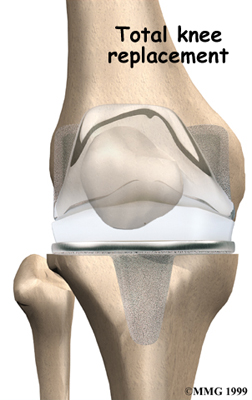

Artificial Knee Replacement

An artificial knee replacement is the ultimate solution for advanced knee OA.

Surgeons prefer not to put a new knee joint in patients younger than 60. This is because younger patients are generally more active and might put too much stress on the joint, causing it to loosen or even crack. A revision surgery to replace a damaged prosthesis is harder to do, has more possible complications, and is usually less successful than a first-time joint replacement surgery.

Related Document: FYZICAL Monroeville's Guide to Artificial Joint Replacement of the Knee